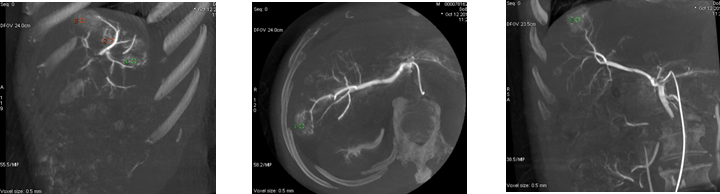

为了进一步详细观察病灶形态和大小,行3D采集,仅需5秒即可完成血管的三维扫描

3D MIP重建不同体位和角度下观察病灶和血管形态